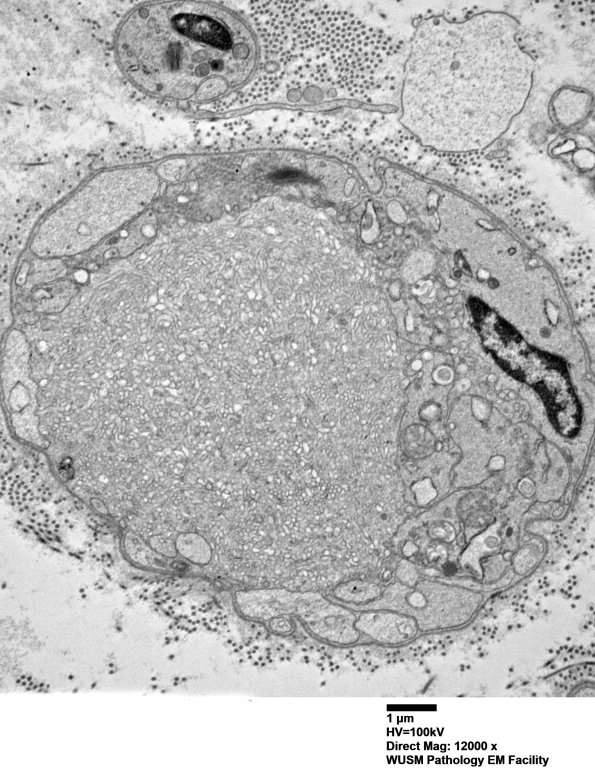

Higher magnification of image #16C7. (electron micrograph)